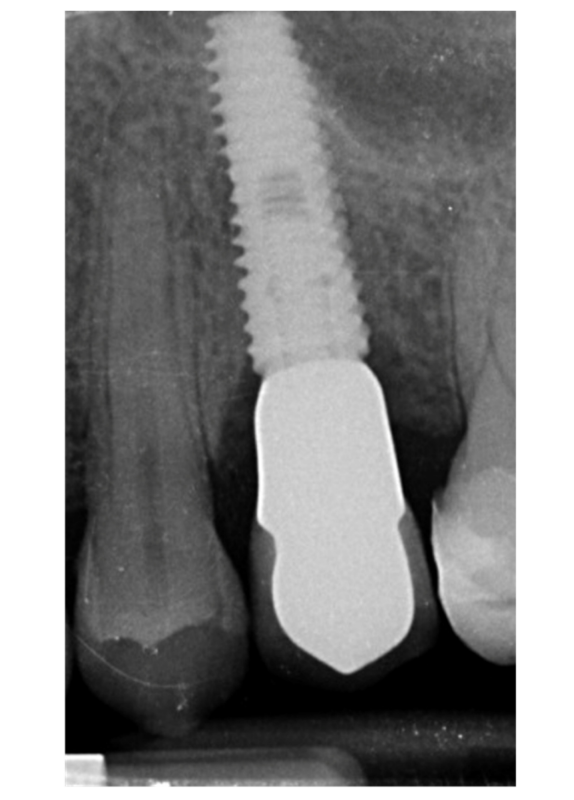

Implants fracture is an untreatable condition. There are several tools that may help clinician to remove the implant. However, fractured implant often presented damaged implant-abutment connection, hence, implant retrieval tools/kits (Figures 1–4) may not work. In cases implant is severely damaged and/or the residual osseointegration is very strong, such us in the mandible, the only possibility is to use a trephine burs (Figures 5–10).